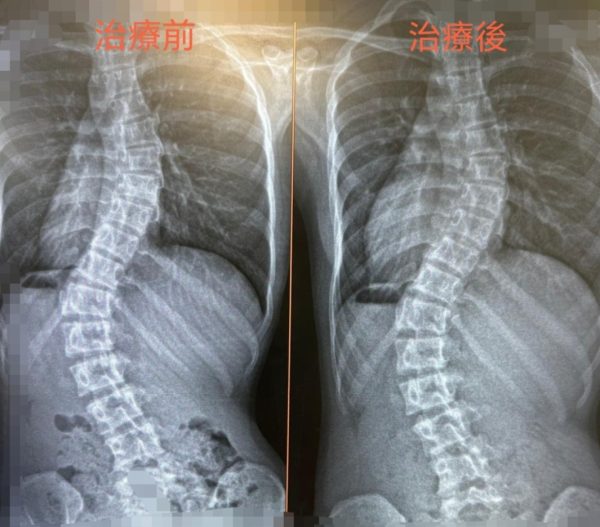

凌小友從去年9月中至今年2月初 (期間因事停診一個月),共進行了3個針灸療程。

2026年2月初西醫復診,結果如下:

脊椎上部,從2025年6月的43度微減至42度。

脊椎下部: 從2025年6月的56.9度明顯減至49度。

治療效果屬於理想。(治療前後對照, 見下圖) 春節稍休後,繼續治療。